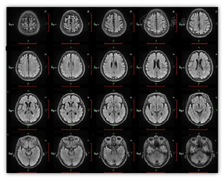

Flair序列显示:双侧脑结构对称,脑灰白质对比正常;双侧额顶叶及双侧侧脑室周围可见少许小斑片状稍长T2高FLAIR信号,相应部位未见明显弥散受限改变;SWI序列显示:脑内未见明显异常低信号影(图1)。